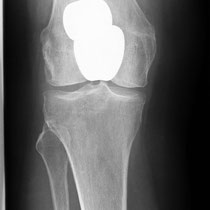

Auch bei dem künstlichen Ersatz des Kniegelenkes muss genau abgewogen werden, was eingentlich ersetzt werden muss. Je weniger ersetzt wird umso besser im Gesamtergebnis. Warum soll man das ganze Knie ersetzen, wenn nur der Knorpel unter der Kniescheibe zerstört ist (Bild 3 Kniescheiben - und Gleitlagerersatz). Anders bei schwerer Rheumazerstörung, bei der alle Bänder ausgelockert sind - hier wäre die normale Knieprothese auch locker (Bild 5 Lösung: achsgekoppelte Prothese). Ich versuche für meine Patienten das bestmögliche Implantat auszusuchen. Für Allergiker stehen spezielle titanbeschichtete Kniegelenke zur Verfügung.